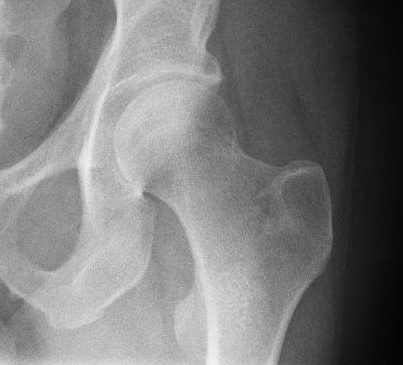

РОЗПІЗНАЙТЕ КІСТКУ. ПЕРЕЛОМ ЯКОЇ ЇЇ ЧАСТИНИ ВИ БАЧИТЕ НА РЕНТГЕНОГРАМІ?

варіанти відповідей

FEMUR, ШИЙКА

ПРОКСИМАЛЬНОГО ЕПІФІЗА

ДИСТАЛЬНОГО ЕПІФІЗА

ДІАФІЗА